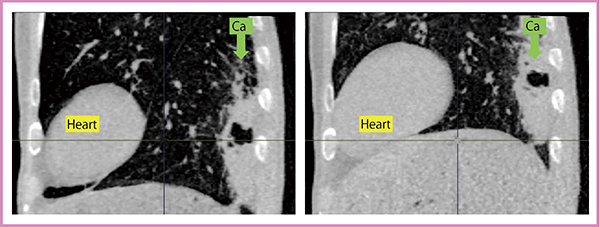

約8年間の研究の成果は,Aquilion ONE本体およびアプリケーションの技術革新とともに,おおまかにいくつかの段階・時期に分けることができる。当初は,Aquilion ONEの最大の特徴である,「16cmのスキャン長(頭尾方向)をガントリ1回転で撮影できる」ことを生かして,ヘリカルスキャニングではなく,step and shootスキャニング(16cm×上・中・下の3回転)で胸部CTを撮影する研究を行った1)〜3)。その結果,「Aquilion ONEを用いてstep and shoot法で撮影すると,画質はヘリカルスキャニングと何ら遜色はない」「さらに心電同期(triggering)を使用すれば,同一の被ばく線量で心拍動アーチファクトがない画像を提供でき,心臓近傍の肺結節影の評価等に有用である」などの研究成果を得た。

図2 呼吸ダイナミックCTによる胸膜下肺腫瘍の観察

呼吸により背側の肺腫瘍が胸壁下を滑るように移動しており,壁側胸膜への癒着や浸潤が存在しないことがわかる(琉球大学医学部附属病院にて撮影)。